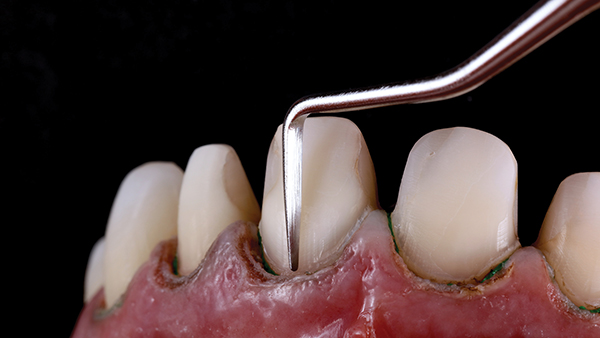

Fig 13. Enamel chisels were used to finalize micro-marginal zones.

Figure 13

After making "depth cuts" through the mock-up, a gingivectomy was performed on the four maxillary incisors. Fine diamonds, gentle pressure, and copious water irrigation limited trauma to vital teeth during preparation. Smooth preparation surfaces and margins enabled optimal fit of the restorations, which is directly correlated with superior clinical success.14 Similarly, the widespread notion that enamel surfaces prepared with coarse diamonds may improve adhesion has long been defied; smooth enamel preparation surfaces, before phosphoric acid-etching, provide significantly better bond strength.15 Enamel chisels were used to finalize micro-marginal zones, making them sharp and visible for the CAD designer and for optimized marginal fit (Figure 13). Proper soft-tissue retraction is needed for an ideal digital impression with an intraoral scanner to create a high-definition and precision digital model. Provisional restorations were inserted after the preparation.